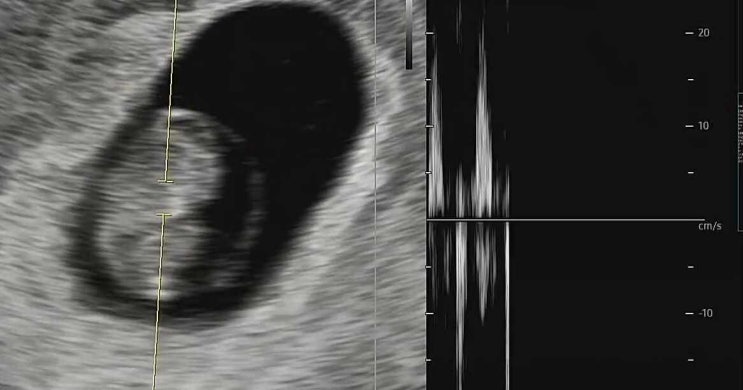

임신 7주차 심장소리 초음파 & 입덧 괜찮아진 이유

1센치도 안되는 크기에 심장이 있고 이렇게나 우렁찬 소리를 내다니 생명의 신비랄까요... 7주차 0일에 산...